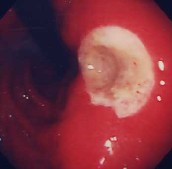

胃ポリープ:

健診の胃X線検査でポリープの疑い、内視鏡検査を施行すると小豆大の白色調の表面平滑なポリープを認めました。組織検査では過形成性ポリープの診断。このポリープは、大きくなったり癌になったりすることはありません。年に一度の検査で十分と思います。